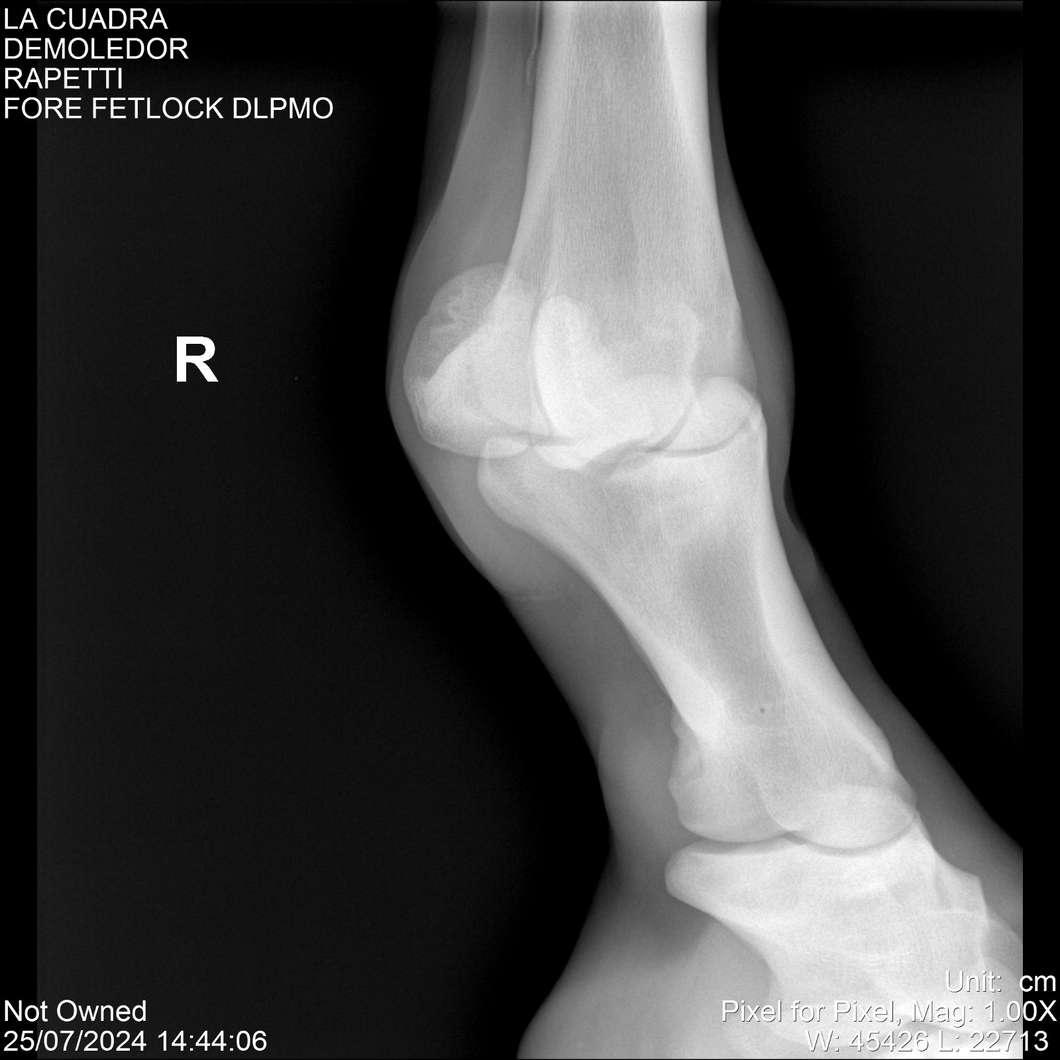

LOTE 14, DEMOLEDOR 🔥 🔥 🔥 Lote Anterior Volver al remate Lote Siguiente Ficha Contacto Montevideo - Ficha del Lote Identificador: #284454 Categoría: Yeguarizos Montevideo - 89 Visualizaciones ClicData Contacto Empresa: Abelenda N. R., Walter Hugo Nombre*: Teléfono* : E-mail* : Mensaje Enviar Registrese gratis Este contenido Exclusivo está disponible sólo para usuarios registrados Ingresar